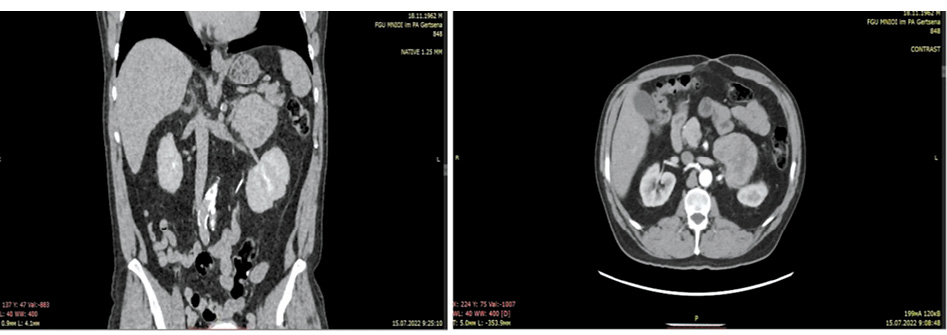

Микроскопическое описание опухоли. В надпочечнике метастаз аденогенного рака криброзно-железистого строения, с обширными очагами некроза, без экстракапсулярного распространения (рис. 2). Хирургический край резекции без опухолевого роста. Заключение: морфологическая картина соответствует вторичному поражению надпочечника – метастазу умеренно дифференцированной аденокарциномы толстой кишки.

Рис. 2. Метастаз умеренно дифференцированной аденокарциномы кишечного типа в надпочечник. ×10, окраска гематоксилином–эозином.

Fig. 2. Metastasis of moderately differentiated intestinal adenocarcinoma to the adrenal gland. ×10, hematoxylin-eosin staining.